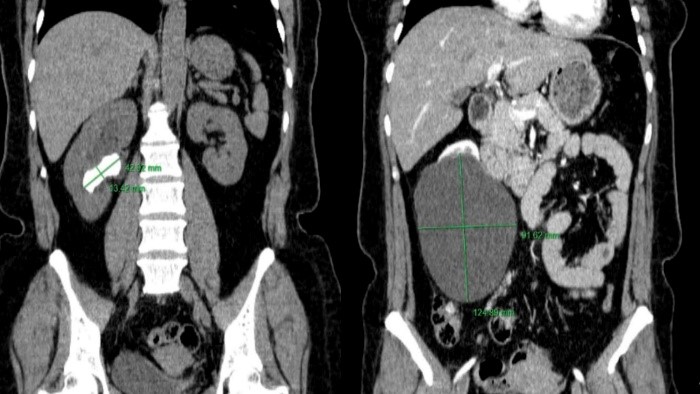

Hình ảnh sỏi thận và nang thận trên phim chụp cắt lớp vi tính và sau phẫu thuật của người bệnh

Nang thận đơn thuần và sỏi bể thận là hai bệnh lý có dịch tễ học khá phổ biến nhưng nhưng hiếm khi xuất hiện đồng thời, do vậy mà các tài liệu về việc lựa chọn phương pháp can thiệp cùng lúc hai bệnh lý này trong một cuộc phẫu thuật cũng rất ít. Thông qua hai ca lâm sàng cụ thể, Tiến sĩ Nguyễn Minh Tuấn – Trưởng khoa Phẫu thuật Tiết niệu cùng ê kíp của mình đã lựa chọn phương pháp ít xâm lấn là phẫu thuật nội soi sau phúc mạc để tiếp cận vấn đề – Phương pháp này giúp hạn chế mất máu, rút ngắn thời gian hồi phục và đặc biệt là điều trị được đồng thời cả hai bệnh lý trong cùng một lần phẫu thuật. Các bệnh nhân đều hồi phục tốt, ra viện sau 5 ngày và không gặp biến chứng sau mổ!